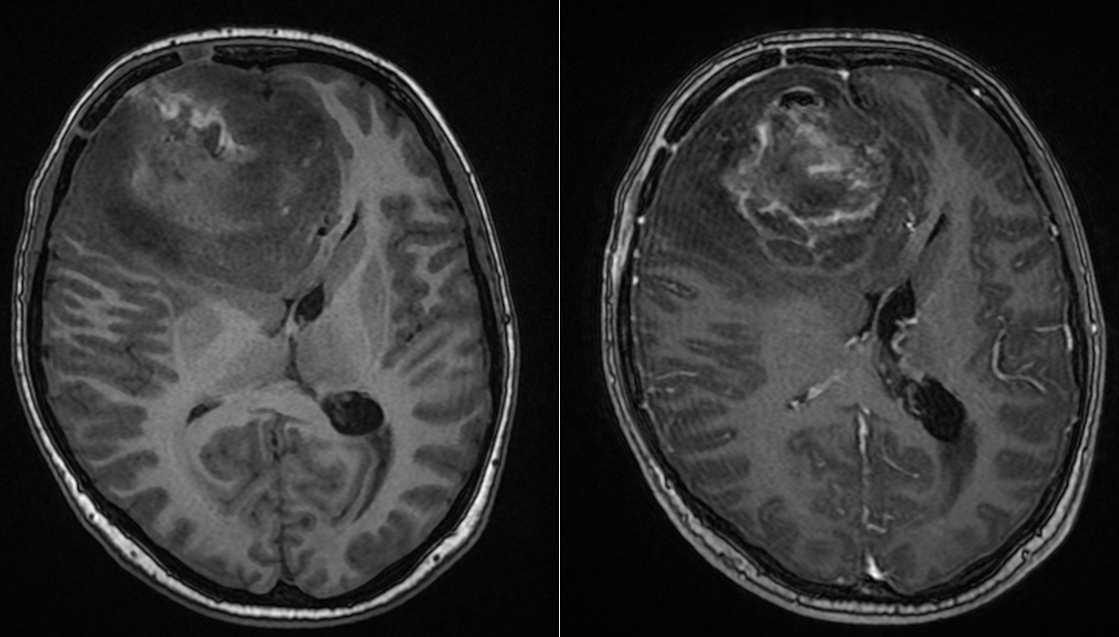

Sub tratamentul chimioterapic, evoluția a fost favorabilă.

RMN-urile succesive au arătat:

- absența progresiei leziunii

- stabilitate imagistică

- lipsa transformării către un fenotip agresiv

La 10 ani de la diagnosticul inițial, situația este remarcabilă:

- fără progresie tumorală, în condițiile tratamentului intermitent cu Temozolomidă.

- boală controlată imagistic

- stare neurologică bună